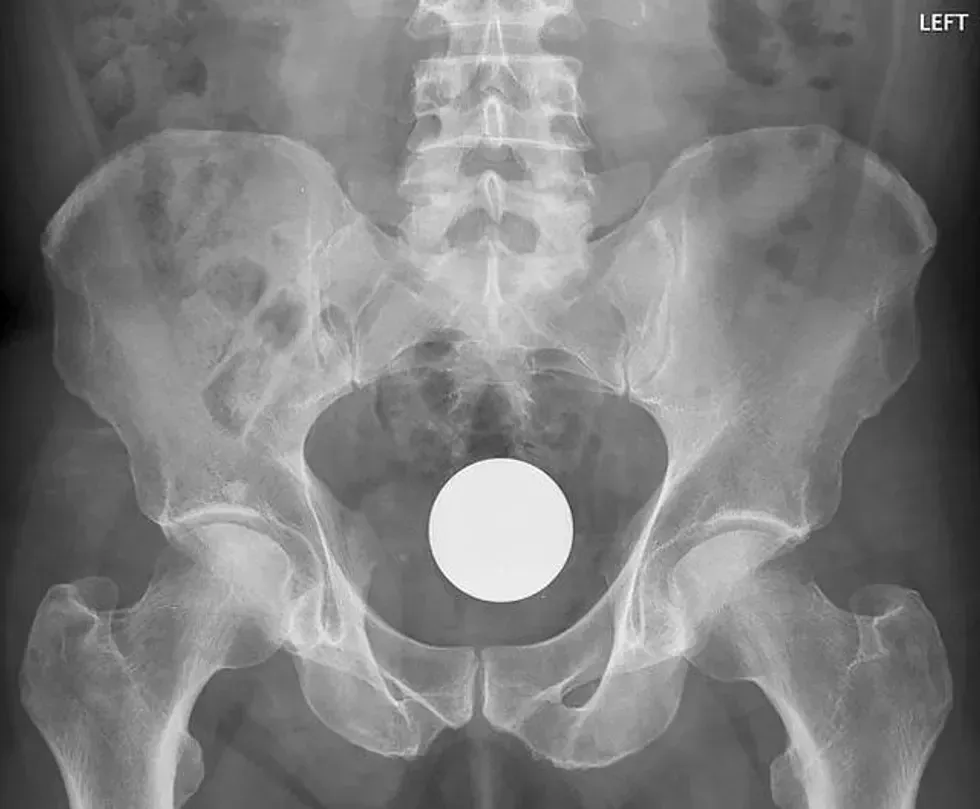

20. A billiard ball